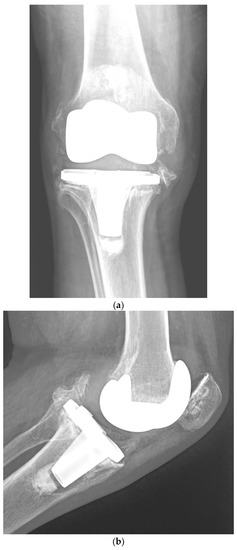

Although one-stage revision TKA is performed in certain situations and centers, a PJI usually requires a two-stage revision TKA, which involves a double surgical intervention. First, the removal of the infected implant (septic loosening) is required. Following this procedure, a period of several weeks of antibiotic treatment is needed until the infection is considered cured (normalization of the ESR and CRP and healing of the surgical wound). The second intervention is the insertion of a new implant, using a model that is stable for proper functioning of the knee [11]. Figure 1 shows a case of PJI (septic loosening) that was solved by a two-stage revision TKA.

Figure 1. (ad). Periprosthetic joint infection of a primary total knee arthroplasty (TKA) that was resolved by a two-stage revision TKA: (a) preoperative anteroposterior (AP) radiograph; (b) preoperative lateral image; (c) postoperative AP radiograph showing the prosthesis implanted in the second-stage revision (rotational hinge design); (d) lateral image of the aforementioned prosthesis.